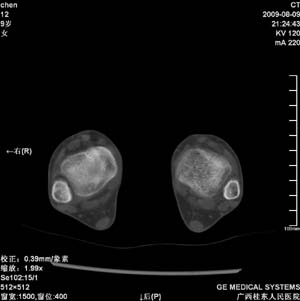

标题: PED2867:右侧内踝肿胀,骨质改变,请各位老师会诊 [打印本页]

标题: PED2867:右侧内踝肿胀,骨质改变,请各位老师会诊

九岁小朋友,近期左侧内踝疼痛,局部肿胀,平时无特殊,近期经常溜干冰

对不起,是右侧内踝肿胀

双侧踝关节骨质及关节结构均未见明显异常。考虑玩多了累的,休息休息看看吧!